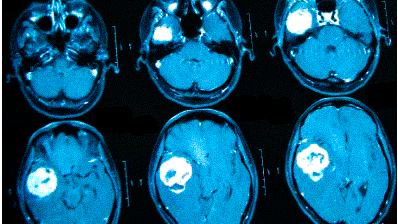

Онкологи считают, что при нарастающих головных болях с прочими необъяснимыми симптомами (обмороками, ухудшением памяти, выпадением полей зрения, давлением на глазные яблоки и др.) в первую очередь следует исключить опухолевую патологию

Частые головные боли вызывают разные причины. Иногда так проявляется серьезное заболевание. В 90% случаев после определения генеза возможно адекватное лечение, которое улучшит качество жизни. Состояния, для которых типична цефалгия::

опухоли;